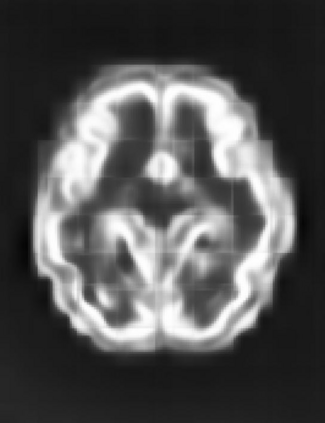

Fetal cortical plate segmentation is essential in quantitative analysis of fetal brain maturation and cortical folding. Manual segmentation of the cortical plate, or manual refinement of automatic segmentations is tedious and time-consuming. Automatic segmentation of the cortical plate, on the other hand, is challenged by the relatively low resolution of the reconstructed fetal brain MRI scans compared to the thin structure of the cortical plate, partial voluming, and the wide range of variations in the morphology of the cortical plate as the brain matures during gestation. To reduce the burden of manual refinement of segmentations, we have developed a new and powerful deep learning segmentation method. Our method exploits new deep attentive modules with mixed kernel convolutions within a fully convolutional neural network architecture that utilizes deep supervision and residual connections. We evaluated our method quantitatively based on several performance measures and expert evaluations. Results show that our method outperforms several state-of-the-art deep models for segmentation, as well as a state-of-the-art multi-atlas segmentation technique. We achieved average Dice similarity coefficient of 0.87, average Hausdorff distance of 0.96 mm, and average symmetric surface difference of 0.28 mm on reconstructed fetal brain MRI scans of fetuses scanned in the gestational age range of 16 to 39 weeks. With a computation time of less than 1 minute per fetal brain, our method can facilitate and accelerate large-scale studies on normal and altered fetal brain cortical maturation and folding.